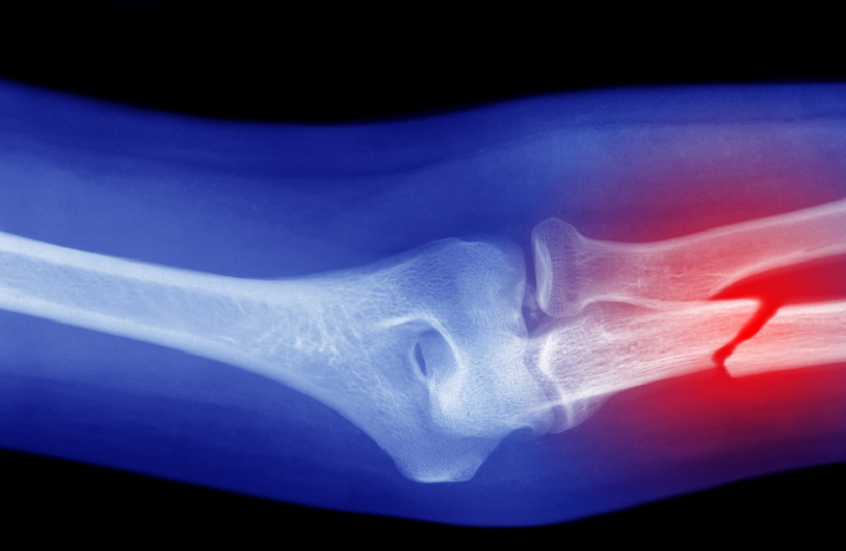

أظهرت دراسة أجراها علماء من جامعة تشيستر البريطانية أن اتباع حمية البحر الأبيض المتوسط قد يقلل من خطر التعرض لكسور العظام.

وأظهرت النتائج أن كثافة العظام لم تتغير بشكل كبير بين معظم متبعي هذه الحميات، ولكن الفوارق كانت مرتبطة بمعدلات الكسور؛ حيث وجد الباحثون أن الأشخاص المتبعين لحمية البحر الأبيض المتوسط كانوا أقل عرضة للإصابة بالكسور، بما في ذلك كسور الورك.